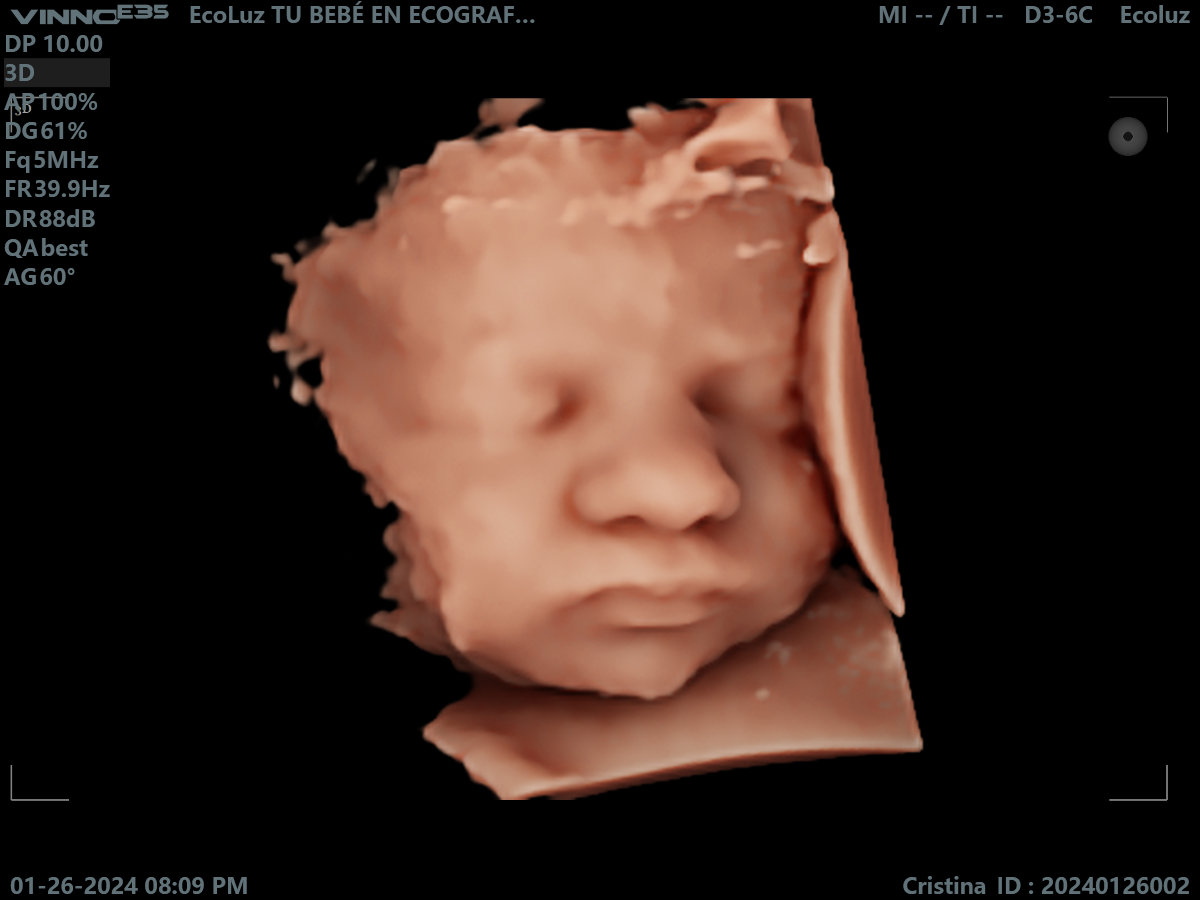

En esta etapa del embarazo, la eco 30 semanas muestra un bebé más grande y con menos espacio para moverse, lo que facilita ver su rostro más fijo en pantalla.…

Muchas familias consideran la ecografía de 30 semanas como una de las más impactantes visualmente. La definición del rostro y los detalles son sorprendentes. 💫 En EcoLuz 5D creamos un…

A las 30 semanas, el bebé ya tiene una expresión muy reconocible. La ecografía 30 semanas permite captar gestos únicos que emocionan a toda la familia.